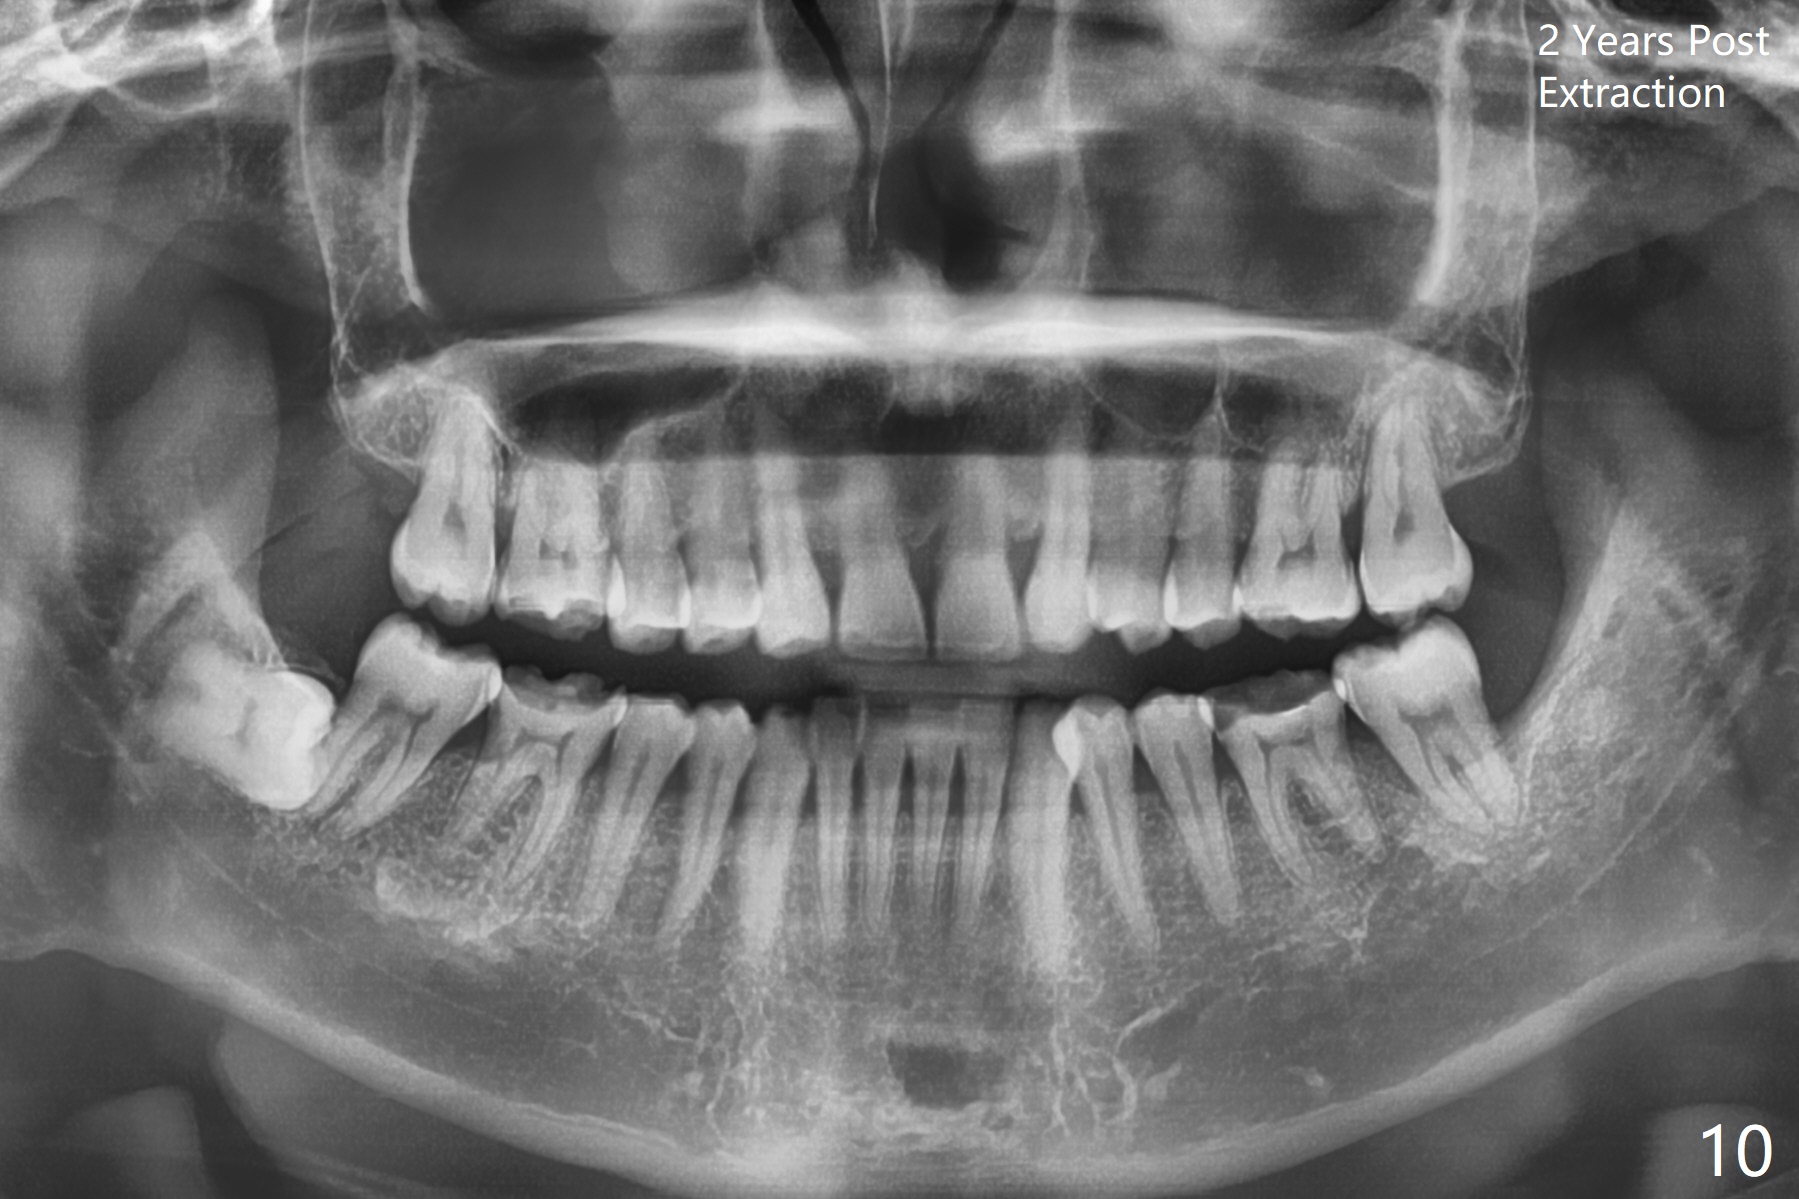

Photos are taken to show occlusal wear (bruxism) of the teeth #31 and 17 (Fig.7,8) prior to #17 extraction. Osteogen plug is placed in #17 socket after extraction and SRP at #18. The bone height at #18 distal seems to increase 2 years 4 months post extraction (Fig.9-12). The 1st molars have enamel hypoplasia with occlusal wear. In addition, occlusion is abnormal. There is no centric occlusion, partially contributing to periodontitis at #15 and 18. Crown is planned at #19 because of loss of occlusal amalgam (Fig.11 A, 12). Orthodontics may be required, although 2 insurances do not have orthodontic coverage for adults.